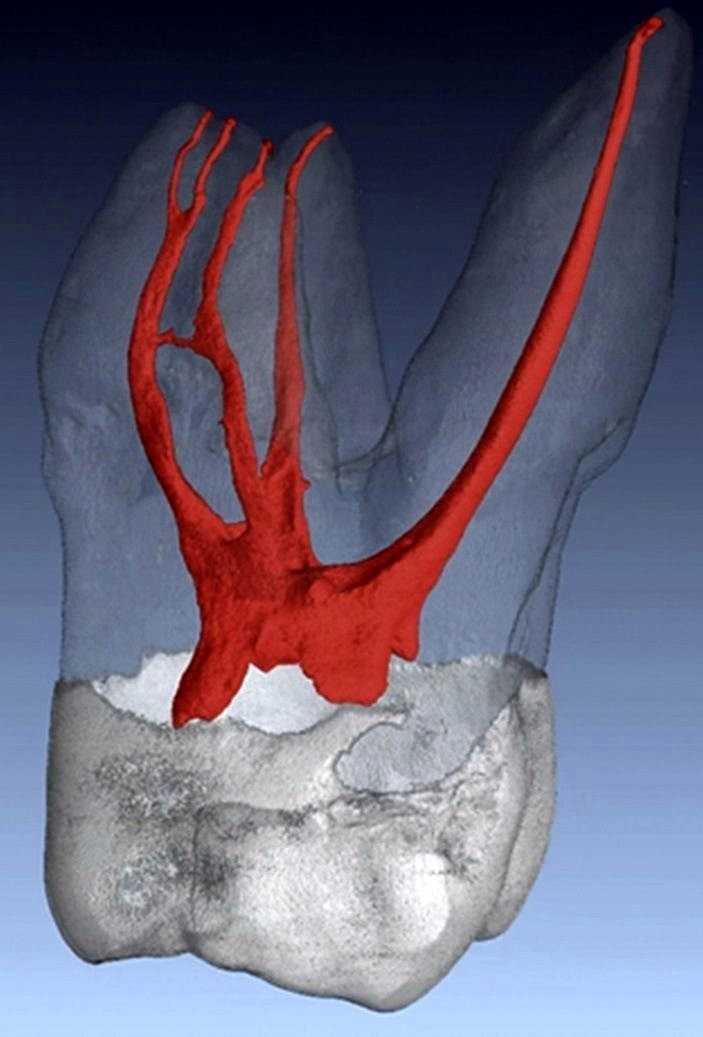

A fog megmentéséhez gyökérkezelés szükséges. Ám a röntgenfelvétel azt mutatja, hogy ennek a bal felső 7-es fognak – mint általában – 3 db foggyökere van (két külső az arc és egy belső a szájpadlás felé), ám az első-külső (ún. mesio-buccalis) foggyökérben 2 db gyökércsatorna is található.

A képen a 3 foggyökérrel rendelkező őrlőfog csatorna rendszere látható.